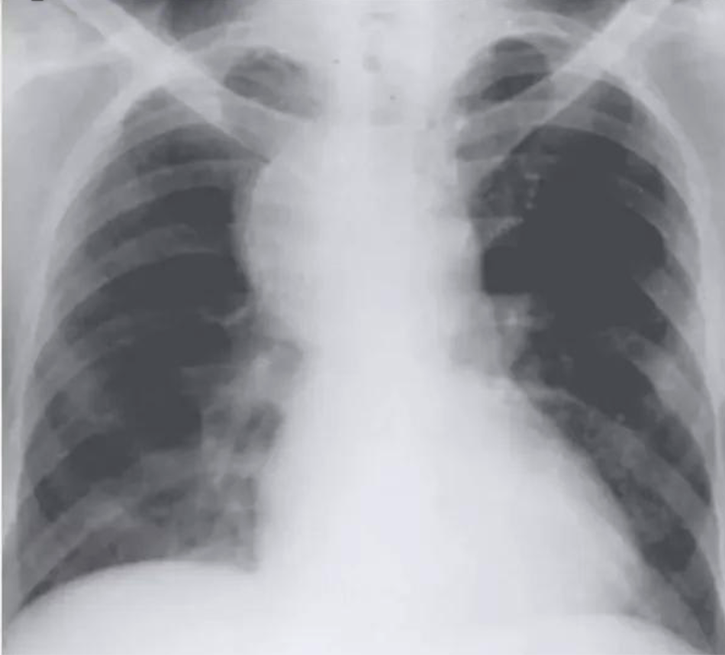

10-year-old child with tuberculosis, shows widening of the right paratracheal stripe

shows a right upper lobe airspace opacity adjacent to the trachea.